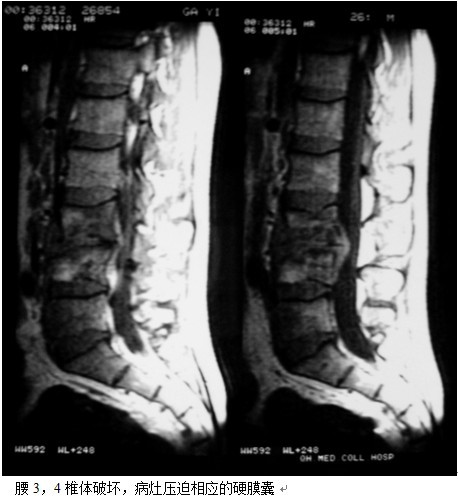

本组46例中男28 例,女18 例。年龄17~67岁,病程6 个月~7年,平均11.3 个月。本组患者均为 L1~S1腰段结核。病灶累及2 个椎体31例(L1-2 6例, L2-3 8例,L3-4 10例,L4-5 5例,L5-S1 2例),3 个或3 个以上椎体15例。合并腰大肌脓肿23列,所有患者均有腰背部疼痛,活动受限,双下肢感觉麻木19例,会阴部感觉减退12例,双下肢肌力减弱12例,腱反射减弱12例,术前后凸角(Cobb 角) <30°者12例, 30°~60°者28 例, >60°者6 例,Cobb角平均32.3°4例患者是二次手术。术前均行X线片、CT或者MRI检查。术后病理检查确诊为脊柱结核。

图11-a术前